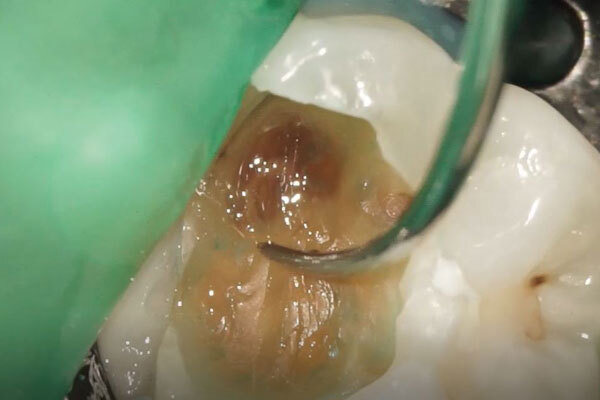

虫歯を全て取り切ると神経が露出しました。

神経の状態をよく観察し、保存が可能であると判断した為、このまま歯髄保存治療を進めることとしました。

露出した面にMTAというセメントを充填し、露出している神経を封鎖します。

その後、MTAがある程度硬化したら仮の材料を詰めていきます。